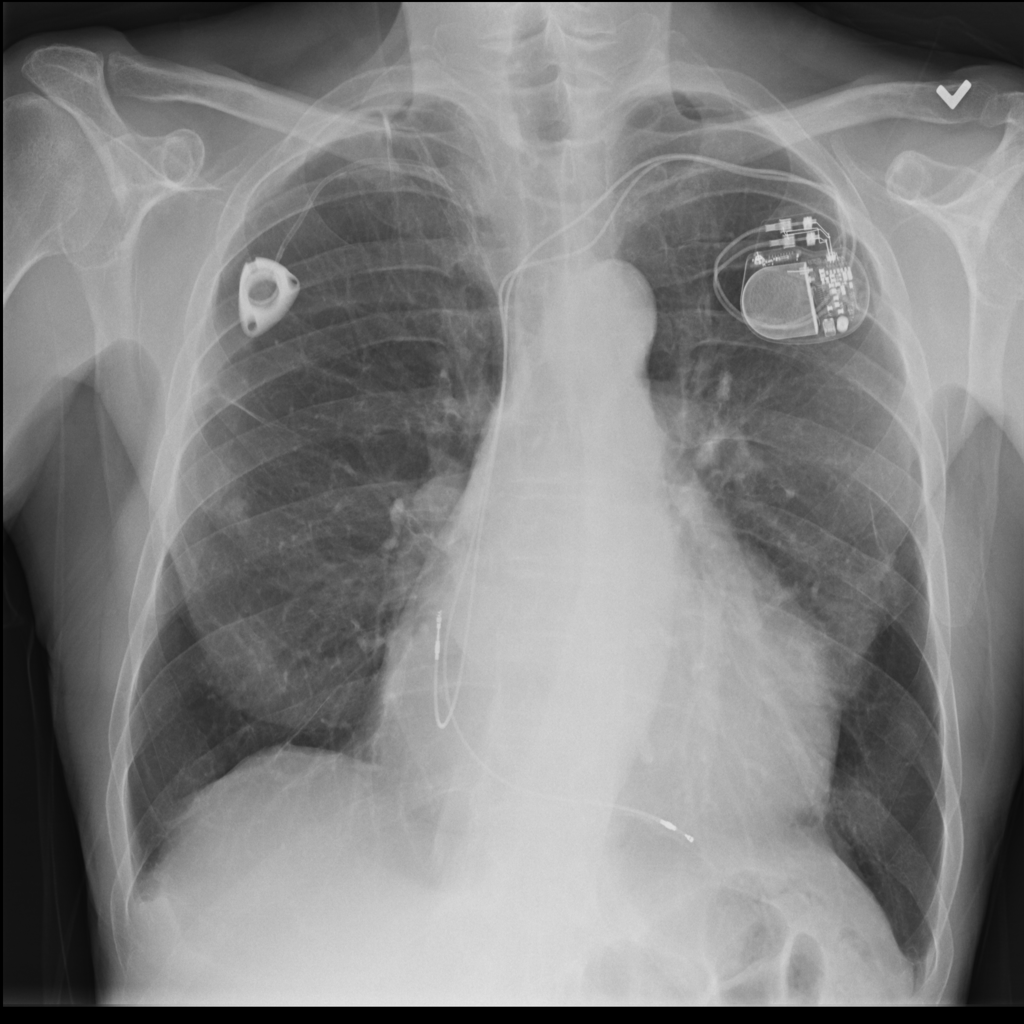

PAT-4639 · IMG-045Cardiomegaly

PAT-4639 · IMG-045

PA